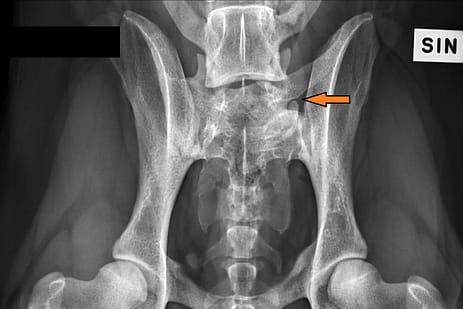

Rhodesiankoirien välimuotoinen lanne-ristinikamia (LTV)